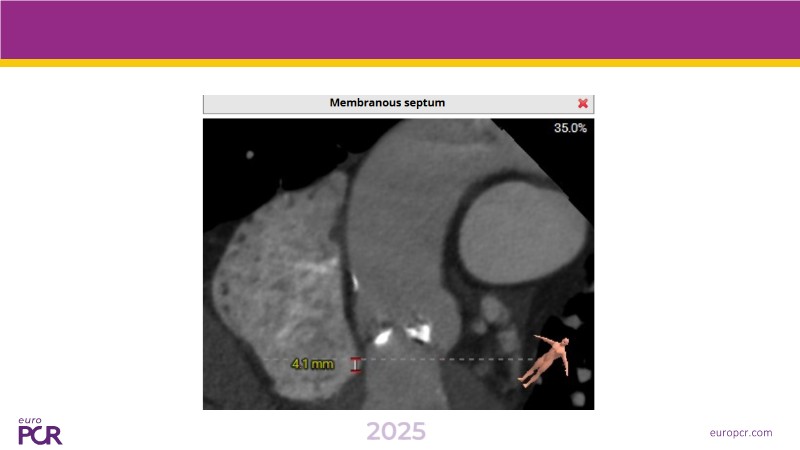

This session presents the latest updates on the novel Myval Octapro transcatheter heart valve (THV), based on one year of real-world clinical experience. Experts share practical tips and clinical cases that highlight how this innovative device can improve TAVI patient outcomes. The session also addresses imaging and sizing strategies critical for TAVI planning, as well as procedural best practices for successful implantation of the Myval Octapro THV.

- To learn from the experts best-in-the-class TAVI practice: pre-procedural (imaging, sizing rationale, treatment strategy), procedural tips and tricks and post-procedural management